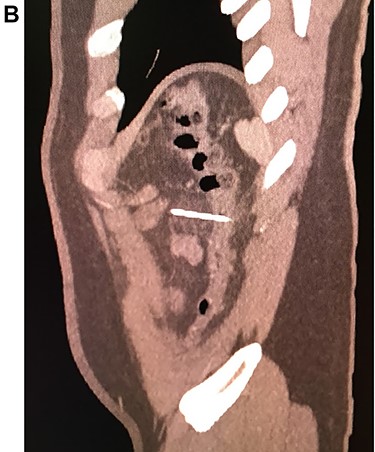

Leukocytosis with neutrophilia was detected, along with an elevated C-reactive protein. On the CT, a high-density object was seen in the descending colon; the object resembled a 4.5 cm needle that perforated the whole extent of the colonic wall. Surrounding this area there was inflammation with mesenteric edema. No lymph nodes or other masses were detected (Fig. 1A, 1B, 1C).